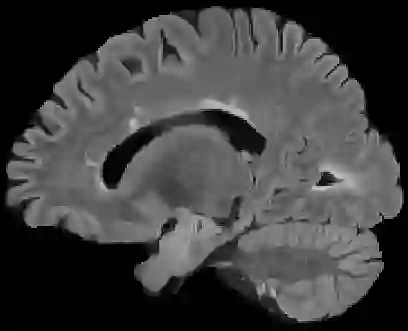

Recently, segmentation methods based on Convolutional Neural Networks (CNNs) showed promising performance in automatic Multiple Sclerosis (MS) lesions segmentation. These techniques have even outperformed human experts in controlled evaluation conditions such as Longitudinal MS Lesion Segmentation Challenge (ISBI Challenge). However state-of-the-art approaches trained to perform well on highly-controlled datasets fail to generalize on clinical data from unseen datasets. Instead of proposing another improvement of the segmentation accuracy, we propose a novel method robust to domain shift and performing well on unseen datasets, called DeepLesionBrain (DLB). This generalization property results from three main contributions. First, DLB is based on a large group of compact 3D CNNs. This spatially distributed strategy ensures a robust prediction despite the risk of generalization failure of some individual networks. Second, DLB includes a new image quality data augmentation to reduce dependency to training data specificity (e.g., acquisition protocol). Finally, to learn a more generalizable representation of MS lesions, we propose a hierarchical specialization learning (HSL). HSL is performed by pre-training a generic network over the whole brain, before using its weights as initialization to locally specialized networks. By this end, DLB learns both generic features extracted at global image level and specific features extracted at local image level. DLB generalization was validated in cross-dataset experiments on MSSEG'16, ISBI challenge, and in-house datasets. During experiments, DLB showed higher segmentation accuracy, better segmentation consistency and greater generalization performance compared to state-of-the-art methods. Therefore, DLB offers a robust framework well-suited for clinical practice.